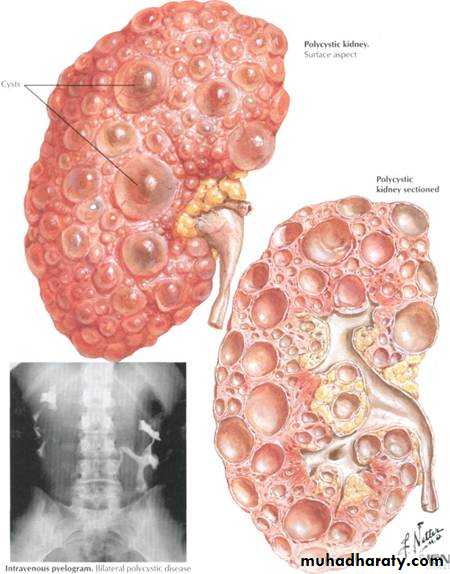

Types of renal abnormalities

1-number2-size

3-position

4-rotation

5-fusion

Congenital abnormalities of renal pelvis and ureter